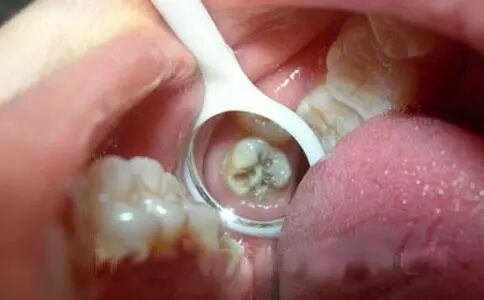

因为蛀牙的表现不仅是疼痛、牙齿表面发黑,有牙洞,而是会深层次的向下发展,慢慢的腐蚀掉整颗牙齿。

而且一般蛀牙已经出现了疼痛的情况,就说明蛀牙已经比较严重了,可能已经随着牙冠位置深入带了牙齿内部组织,常见的情况是由于牙神经受到刺激,引起了蛀牙疼痛的情况,所以这时候需要及时治疗,如果不治疗,会出现严重的牙髓炎以及根尖周炎,甚至最后只能拔掉残根。

龋病发生后,不及时治疗,龋病逐渐向深层发展,牙齿上就会出现肉眼可见的小洞——龋洞,进食酸、甜、冷、热等刺激性食物时会出现牙齿酸痛,如停止进食牙痛马上缓解。